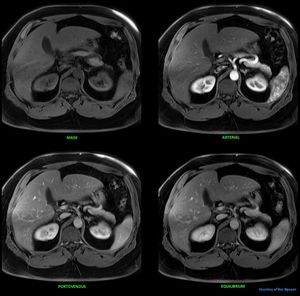

Abdominal imaging dynamic phase @ Siemens 1.5T Aera. This is a 70 bore, even a robust Dixon have problem saturation the fat of this 150kg patient. Imagine what fatsat or spair would suffer of. #Siemens_MRI #mri #siemens #gadolinium #abdominal_liver